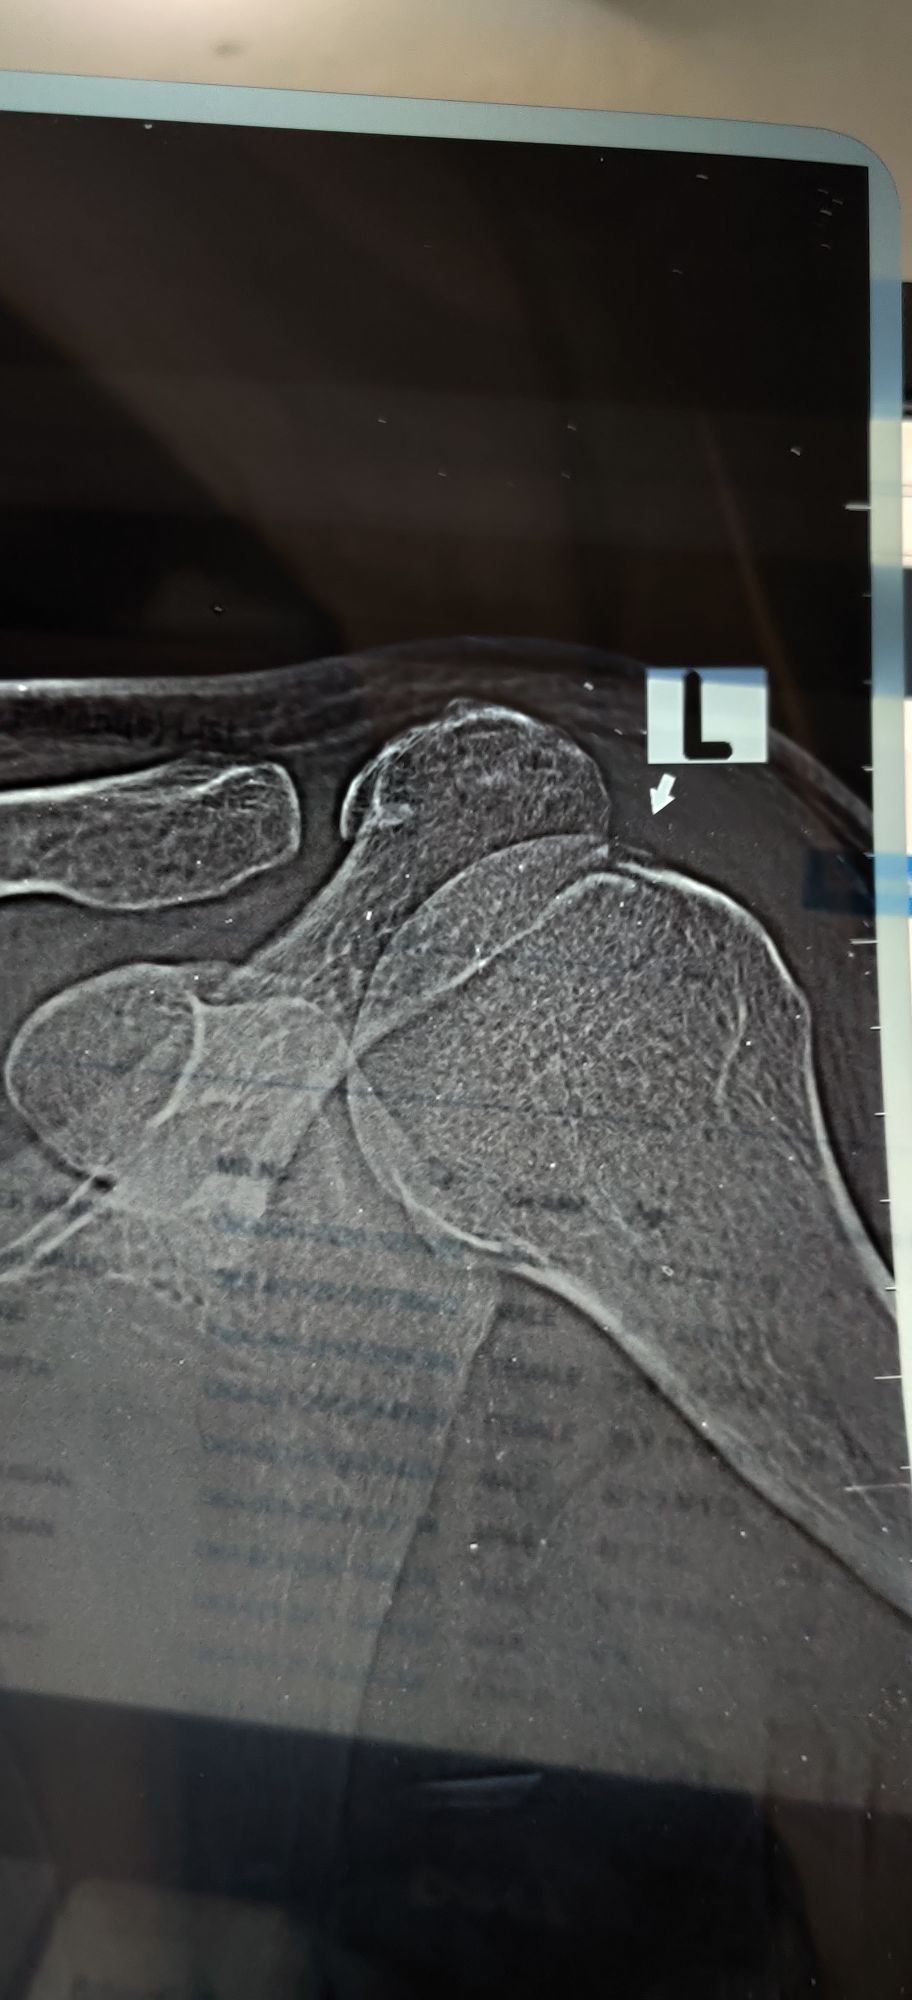

Humerus Fracture / Ligament Avulsion

Xray

Ortho

Rta